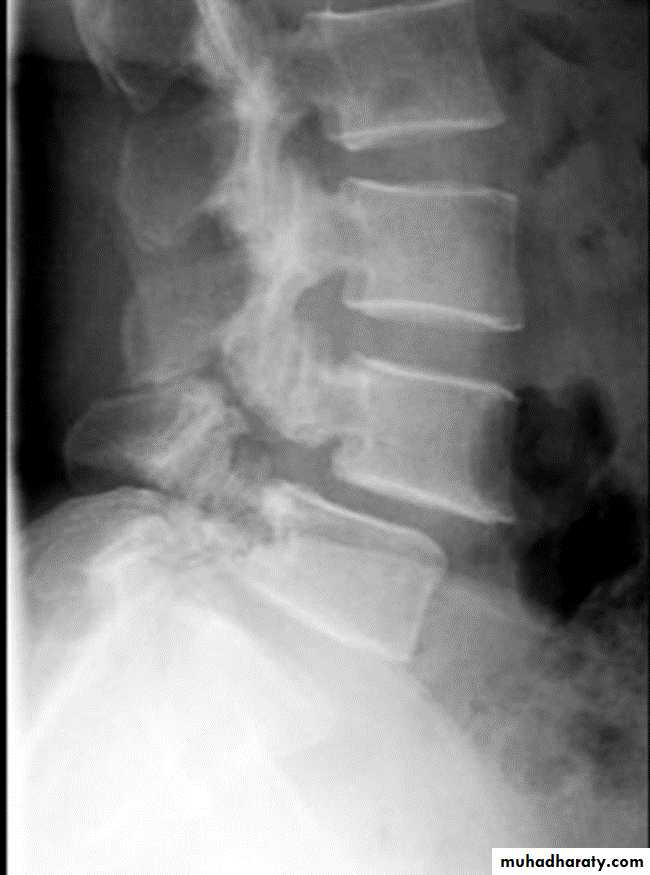

Spondylolysis and spondylolisthesis

Spondylolisthesis: is a term denoting fore ward or backward movement of a vertebra relative to the vertebral segment below, typically due to spondylolysis (pars interarticularis defects) .Spondylolysis: Spondylolysis is a defect in the pars interarticularis of the neural arch, the portion of the neural arch that connects the superior and inferior articular facet in which cause defect in the neck of scotty dog .

scotty dog sign refers to the normal appearance of the lumbar spine when seen on oblique radiographic projection. On oblique views, the posterior elements of vertebra form the figure of a Scotty dog with:

the transverse process being the nose

the pedicle forming the eye

the inferior articular facet being the front leg

the superior articular facet representing the ear

the pars interarticularis (the portion of the lamina that lies between the facets) equivalent to the neck of the dog.